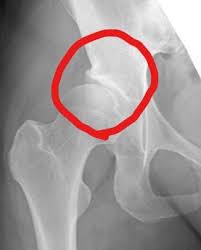

まず、ハッキリとお伝えします。股関節の病気そのものが遺伝するわけではありません。遺伝するのは、股関節の受け皿が浅い「臼蓋形成不全(きゅうがいけいせいふぜん)」という『形』の特徴です。

実は、日本人女性の多くはこの「受け皿が少し浅い」という特徴を持って生まれてきます。受け皿が浅いと、大腿骨(太ももの骨)を支える面積が狭くなるため、一箇所に集中して負担がかかりやすくなります。これが、将来的に「変形性股関節症」へと進行する大きな原因の一つです。